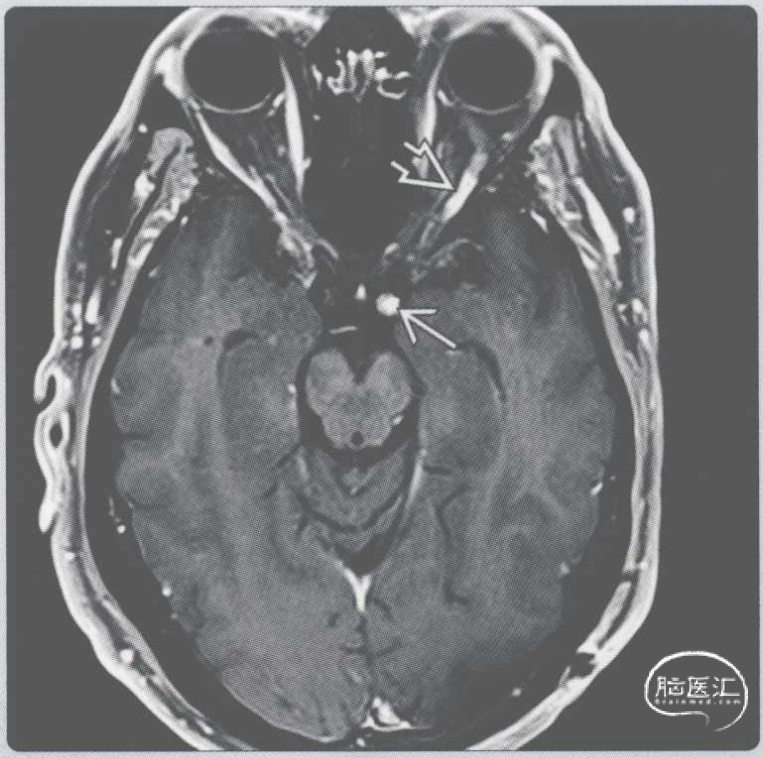

【影像时间·159】一位有复视的食管癌患者